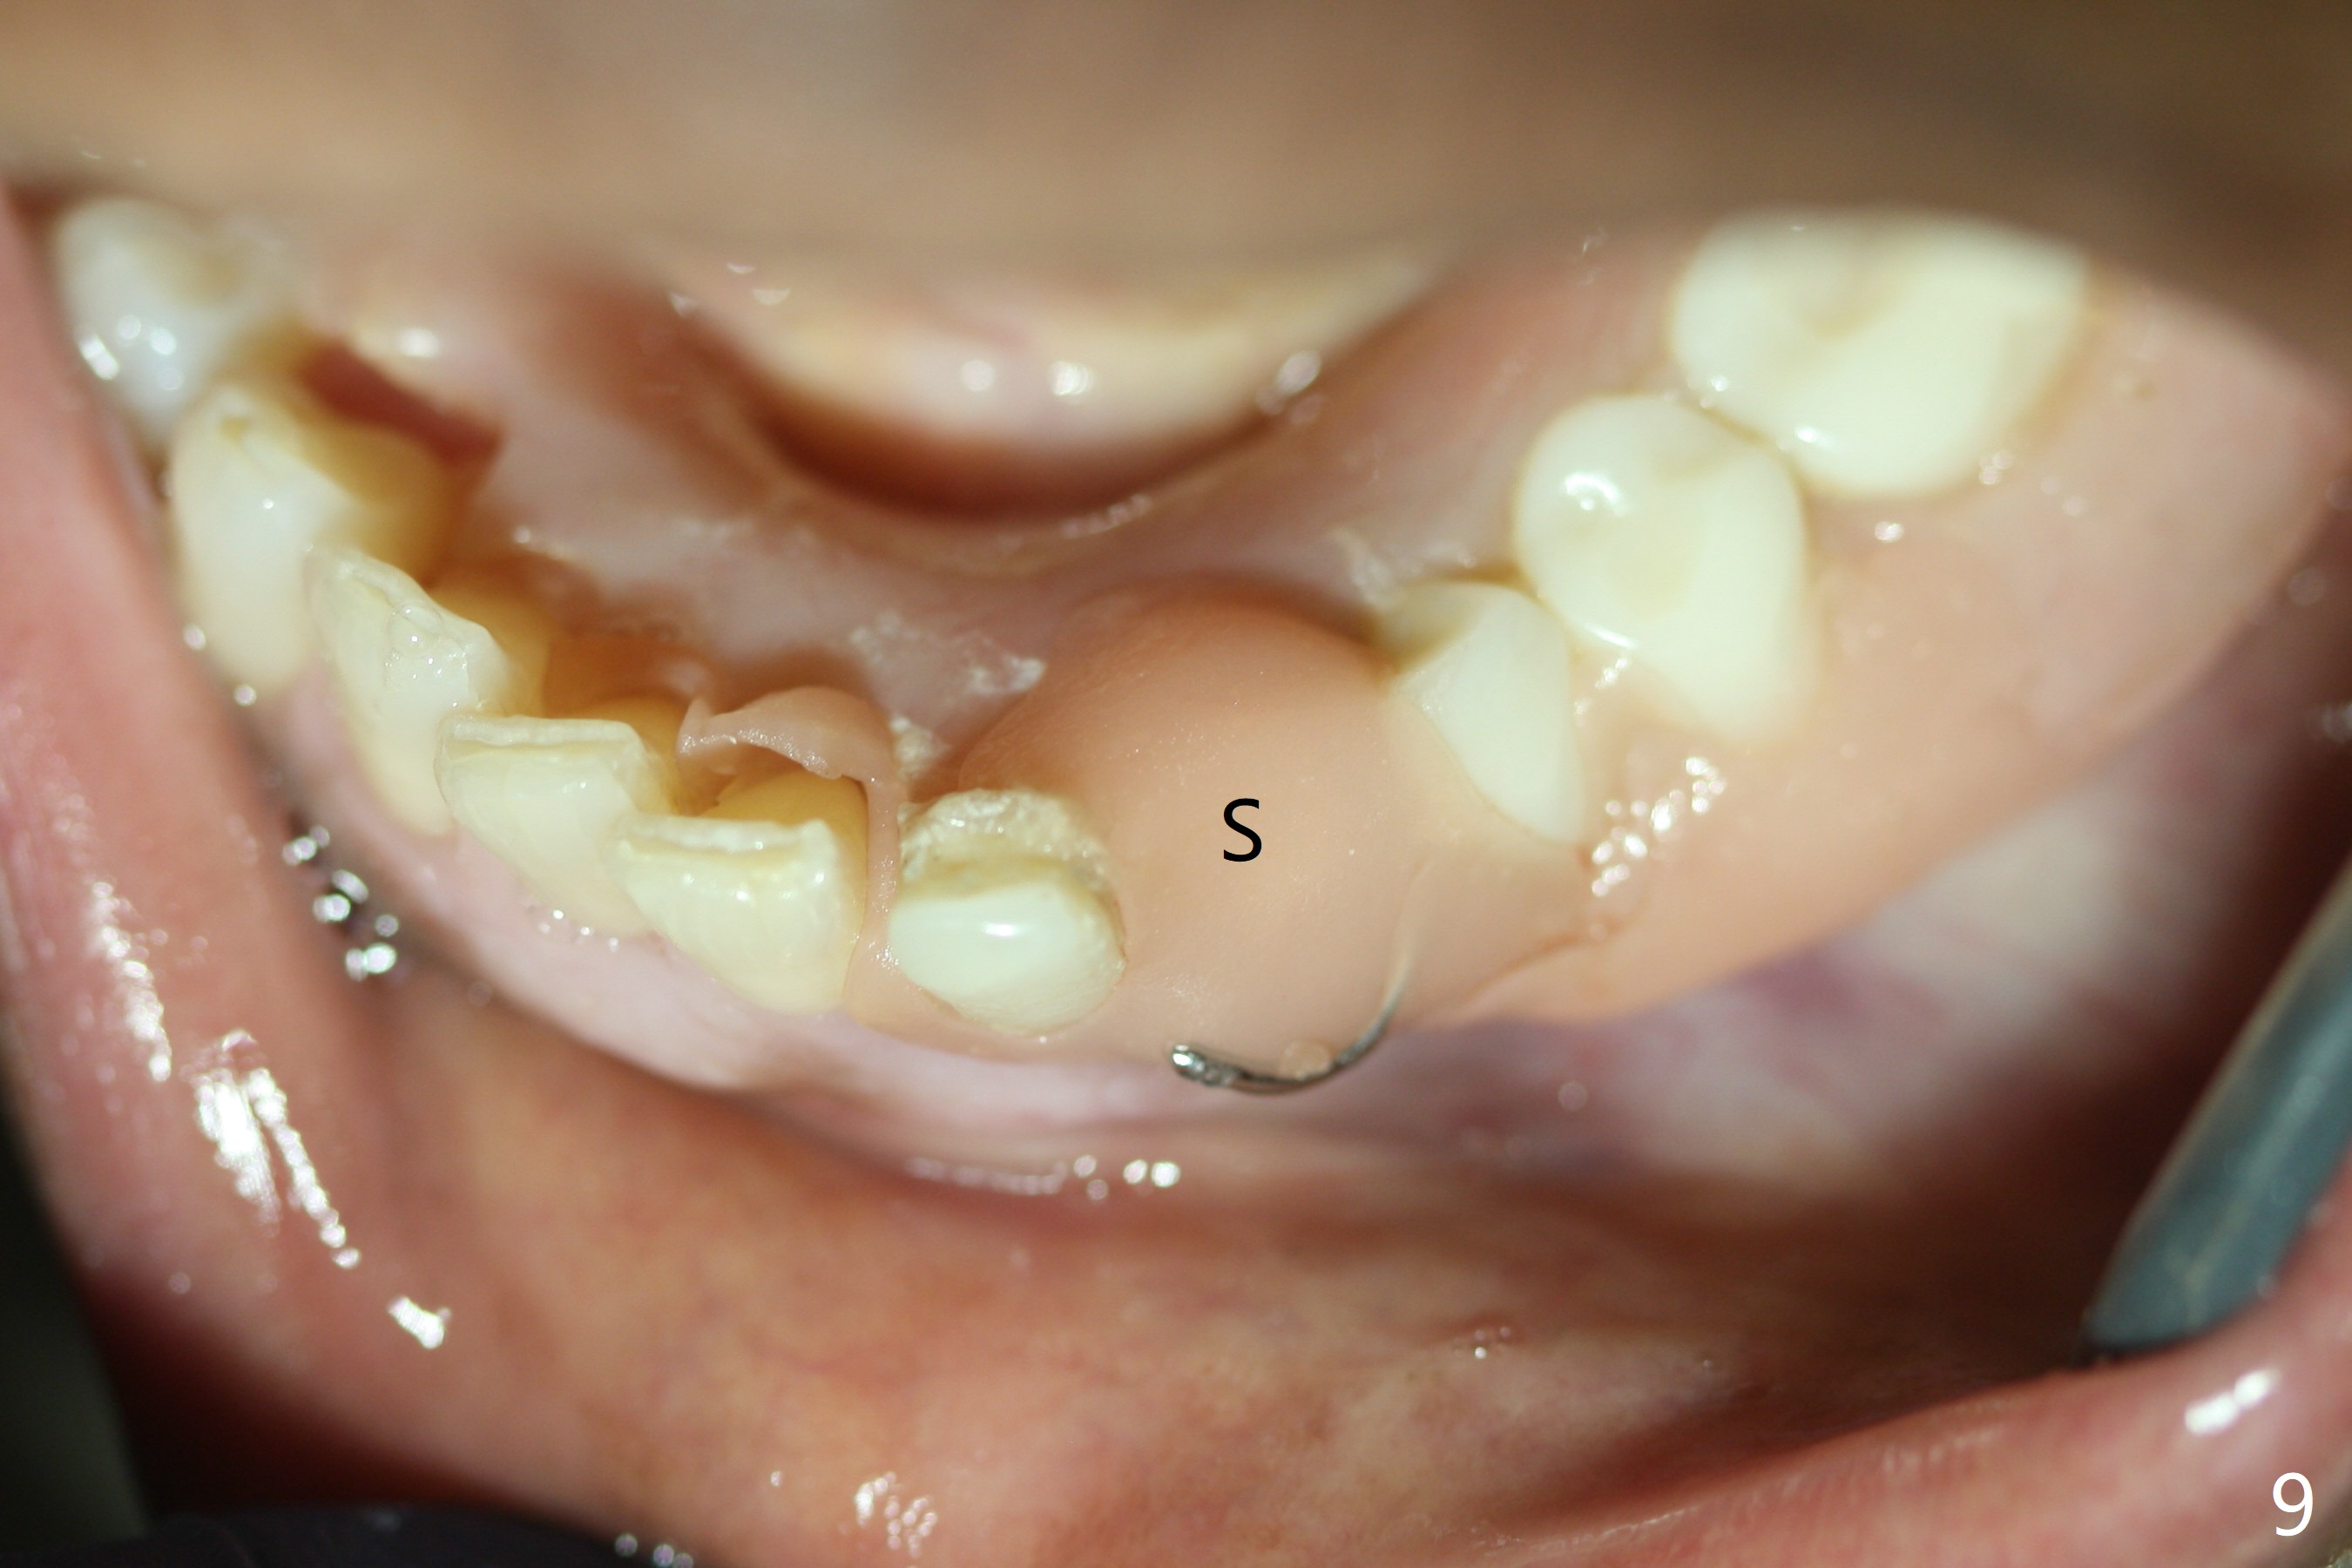

The inflammation around the tooth #22 (Fig.1 *) and mobility may be related to trauma from the only clasp of the lower flipper (Fig.2). The latter is loose with space underneath (>) and laterally (Fig.3 *). The distobuccal plate is defective upon extraction; the osteotomy is initiated in the mesiolingual slope of the socket (Fig.4) with ~ 6 mm native bone. When a 3.8x15 mm dummy implant achieves insertion torque of 50 Ncm, the insertion is incomplete with apical space (Fig.5 *). The definitive implant (3.8x13 mm) closes the apical space and obtains insertion torque >55 Ncm; a ball abutment with 2 mm cuff seems to be short for retention (Fig.6). A 4.5x4(5) mm cemented abutment (Fig.7,8) seems appropriate for retention after soft reline of the lower flipper (Fig.9-11). The socket heals without bone graft exposure 8 days postop (Fig.12,13). To satisfy the patient's desire to have a white tooth, the buccal portion of the soft reline and the abutment is removed (Fig.14) and a crown form is added (Fig.15 *). The socket obliterates 3 months postop (Fig.16).